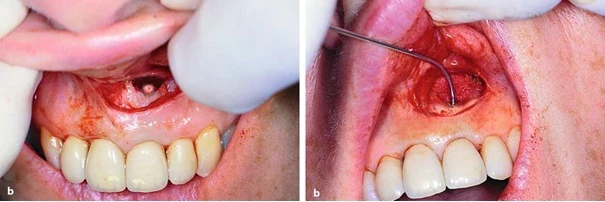

Nhồi chặt chất trám và khâu đóng vết mổ. Quá trình trám ngược phải cầm máu tốt và cách ly xoang cắt chóp bằng bông gạc nhằm ngăn ngừa chất trám rơi vào lòng xoang cắt chóp.

Một vài hình ảnh biến chứng của phẫu thuật cắt chóp

Hình ảnh so sánh một ca cắt chóp trám ngược tốt với chất trám bít kín chóp răng và một trường hợp để rơi chất trám ra mô quanh chóp.

Nhiễm sắc niêm mạc quanh chóp răng tương ứng do rơi vãi almagam ra mô mềm quanh chóp (hình xăm almagam)